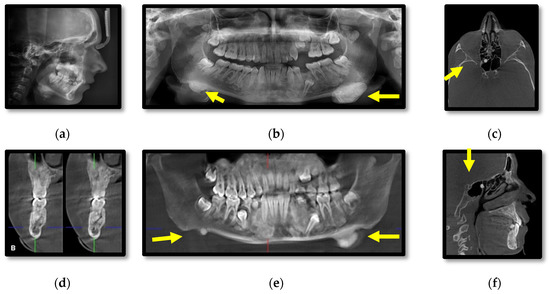

3.1. Radiographic Assessment

4.2. Osteomas

4.3. Dental Abnormalities